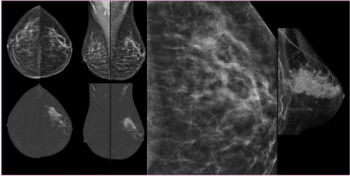

In the third part of a three-part interview from the recent RSNA conference, Mark Traill, M.D., discusses the potential of image-based risk assessment artificial intelligence (AI) algorithms in bolstering adherence to screening protocols for women at high risk for breast cancer.